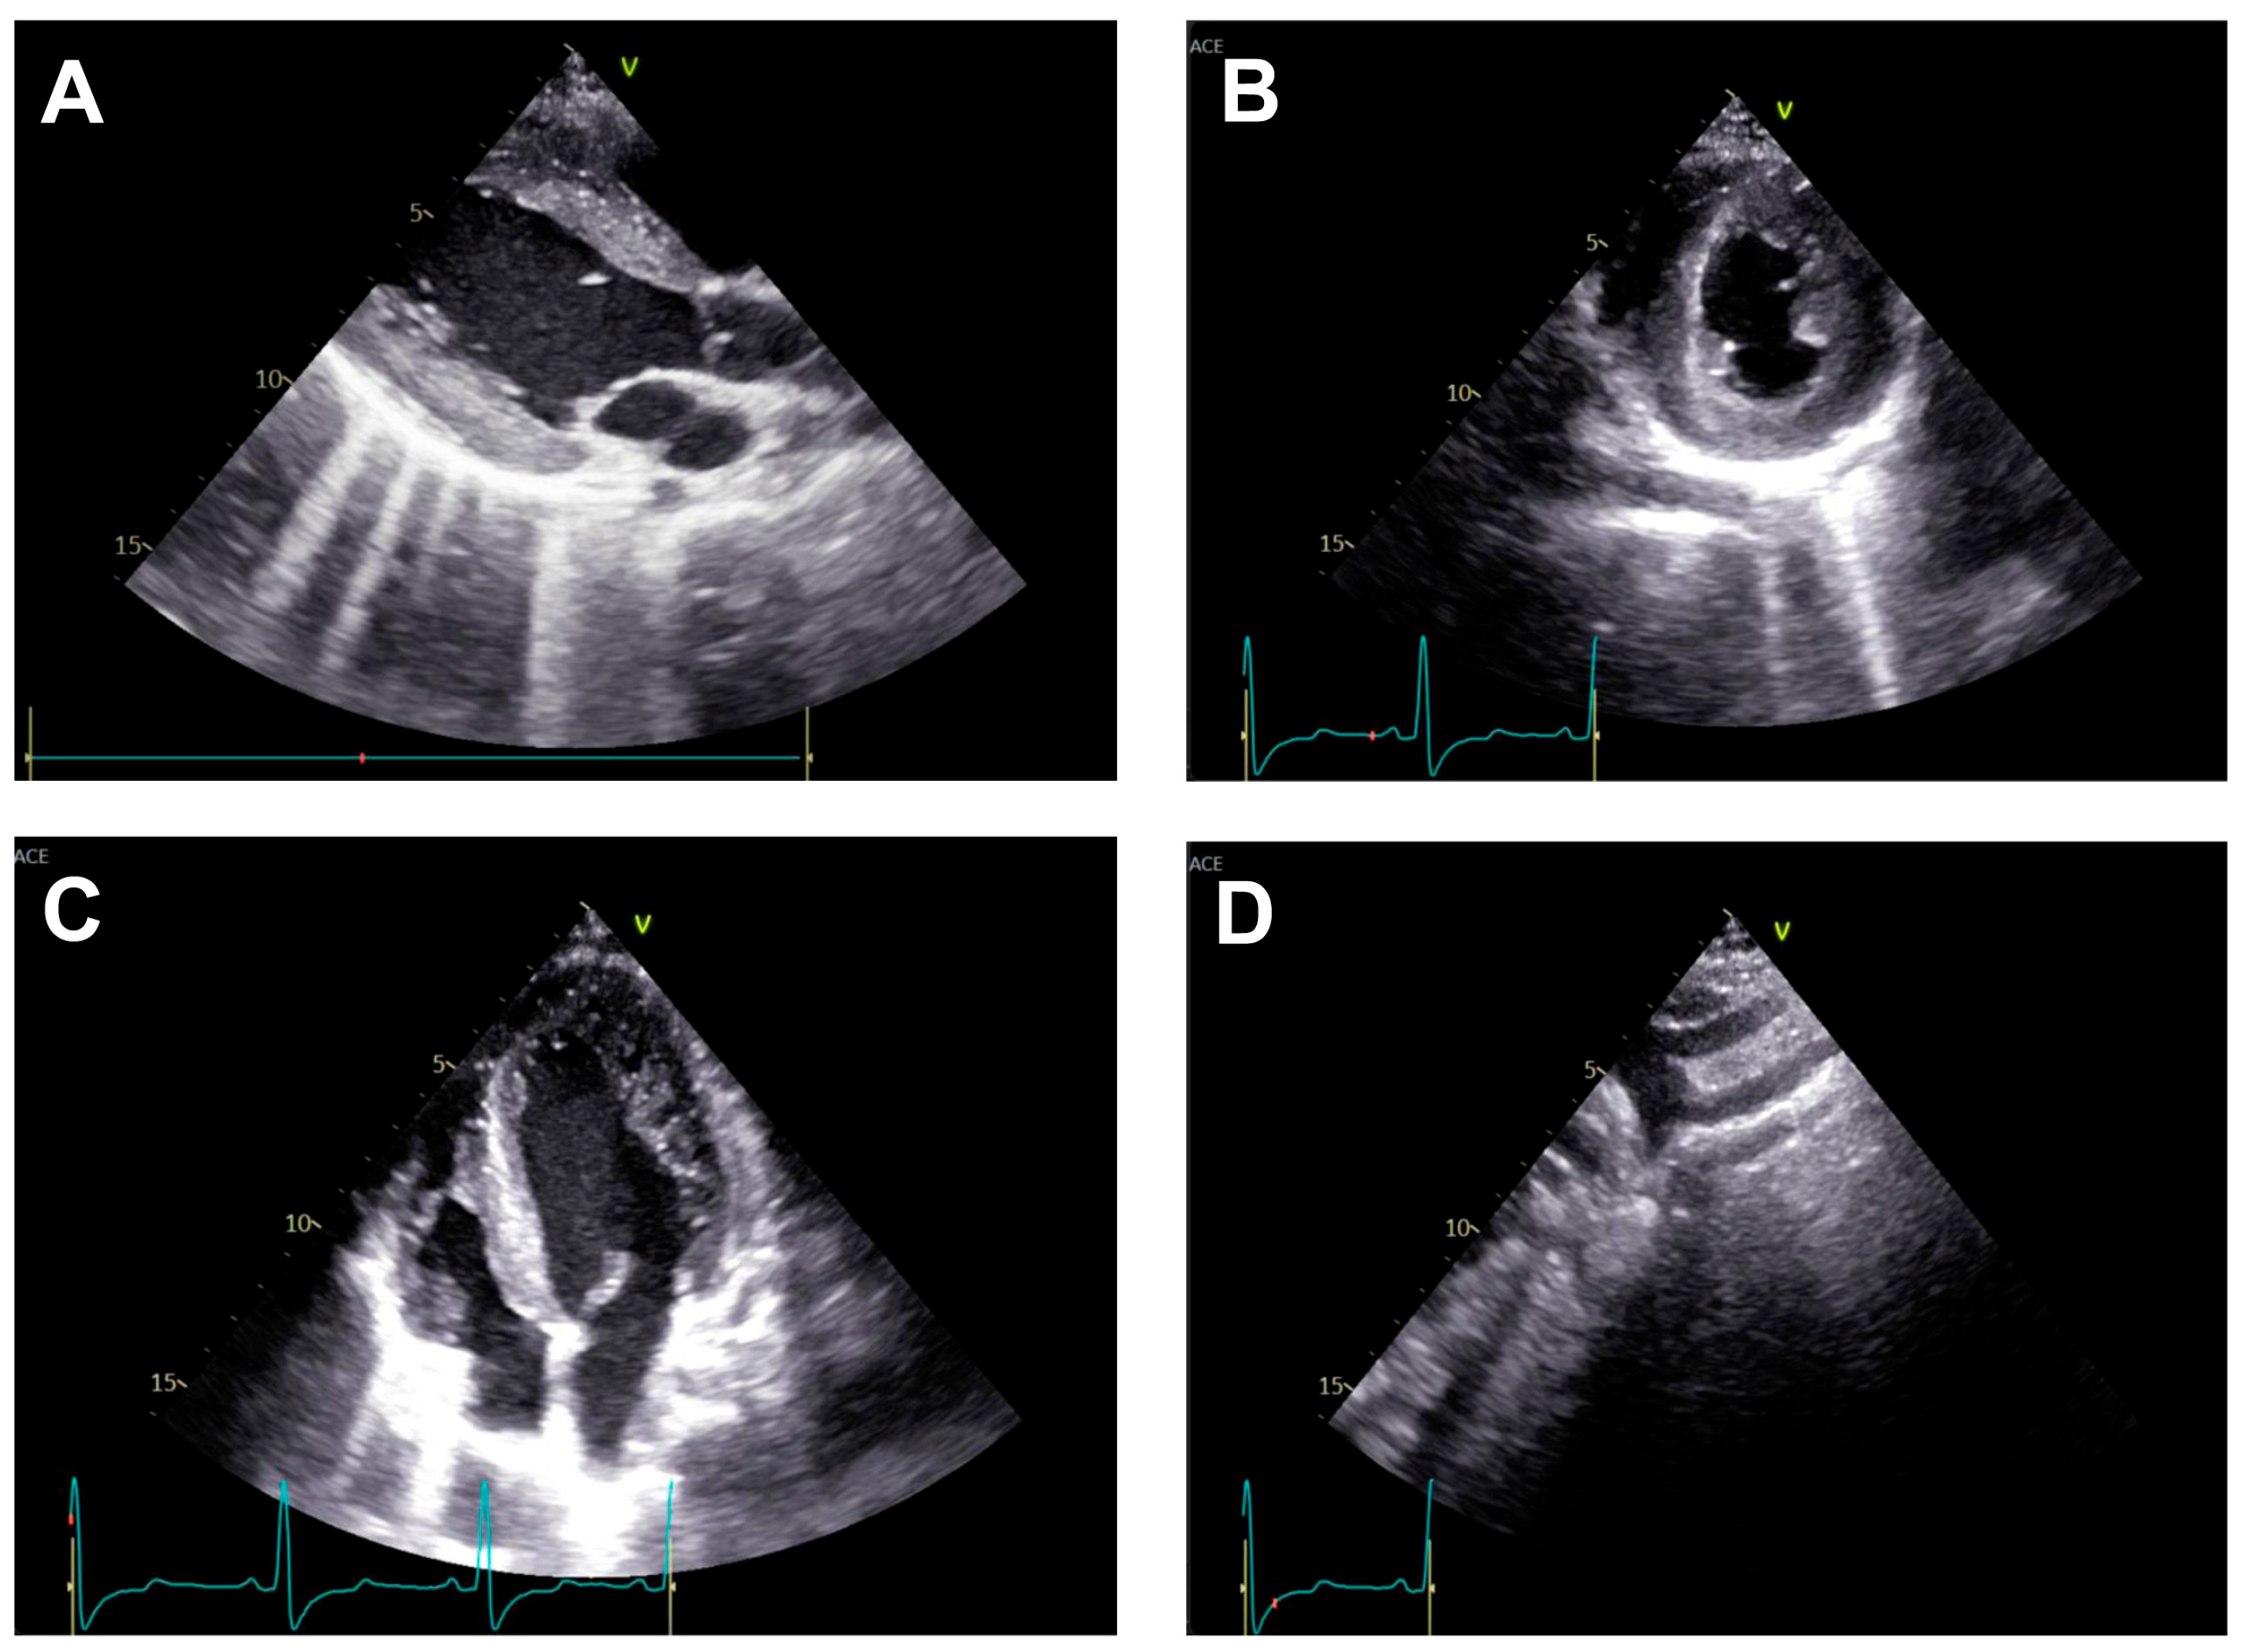

Transthoracic echocardiography (Figure 2) may reveal signs of left ventricular hypertrophy and diastolic dysfunction from the apical and parasternal views, while the suprasternal view may identify the aortic atretic segment. However, the presence of collateral circulation is difficult to identify using this technique [21].